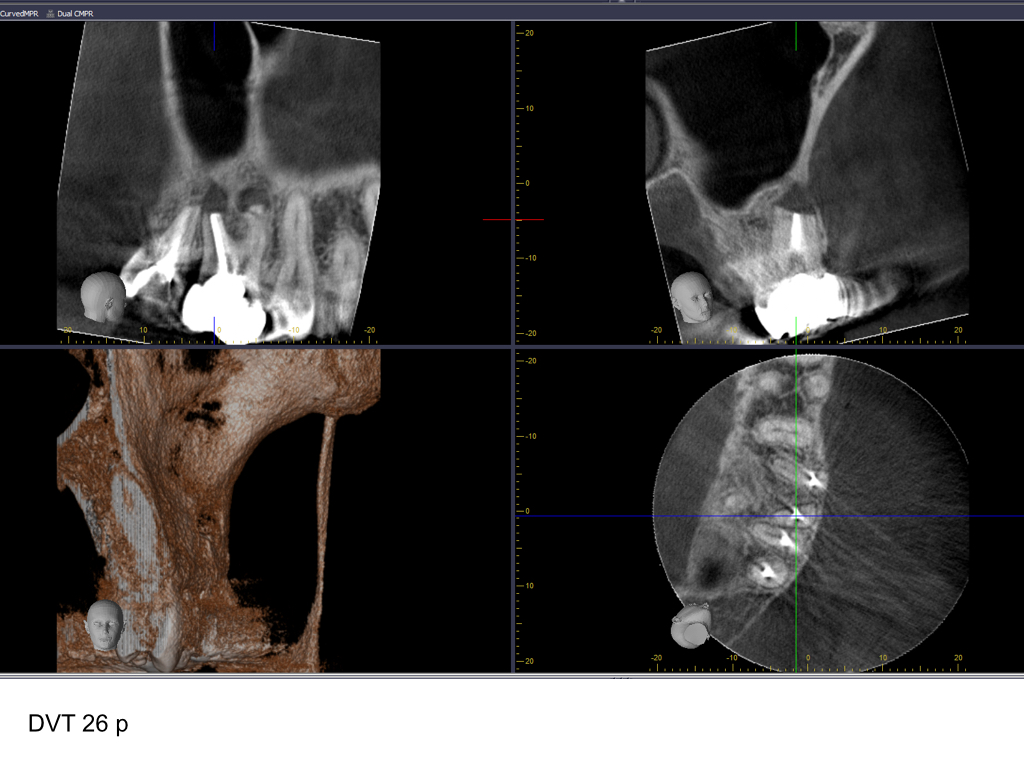

WS15_10.010

Zustand nach WSR